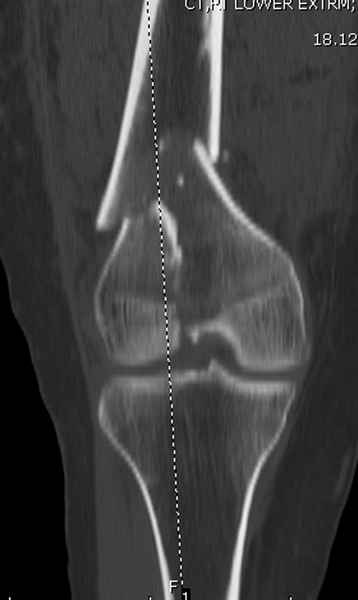

При наличии различных имплантов, любые варианты: слева (полу) открытым - мининвазивным, а справа закрытым интрамедуллярным методом, его считаем более чем приемлемым для фиксации данных переломов.

Проксимальная и дистальная блокировка, независимо от техники введения штифта, ретроградно или антеградно, гарантирует сращение сегментарных переломов бедра без укорочения. Штифты диаметром 12 мм с блокировкой сверху и вниз двумя шурупами выдерживают вес 75 кг больного, что позволяет раннюю профилактику контрактур.

Погоня за "красивой рентгенограммой" не всегда оправдана для фиксации кости, где имеется массивное мягкотканое покрытие. Если так уж хочется исправить положение кости, то при наличии ЭОП, большие костные фрагменты могут быть развернуты или приближены к основному фрагменту методом применения Joystick.

Главное в лечении сегментарных переломов - необходима осторожность при рассверливании канала, продвижение гибкого сверло через сегмент проводят без сверления, толканием, а то были случаи, когда весь сегмент крутился вместе со сверлом.

Из-за вариабельности установки дистальных шурупов и возможности перкутанного введения проксимально предпочитаем DePuy Polyax, хотя на сегодняшнем маркете множеств вариантов фиксации дистального бедра перкутанном методом.